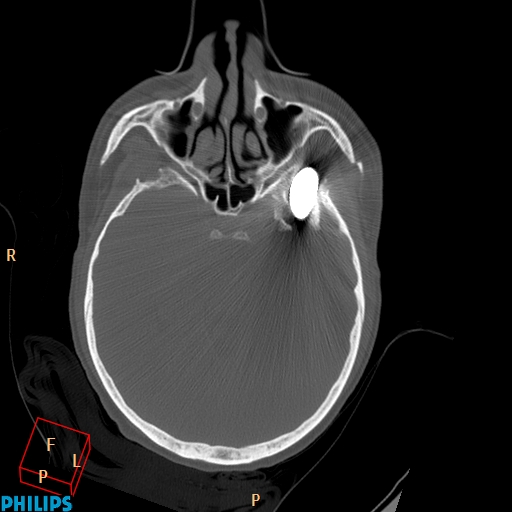

Accident de travail, chute sur une barre de fer. La barre de fer a été coupé sur le chantier pour dégager le patient A noter, comme on peut le voir sur la dernière image, que le patient était conscient et réveillé